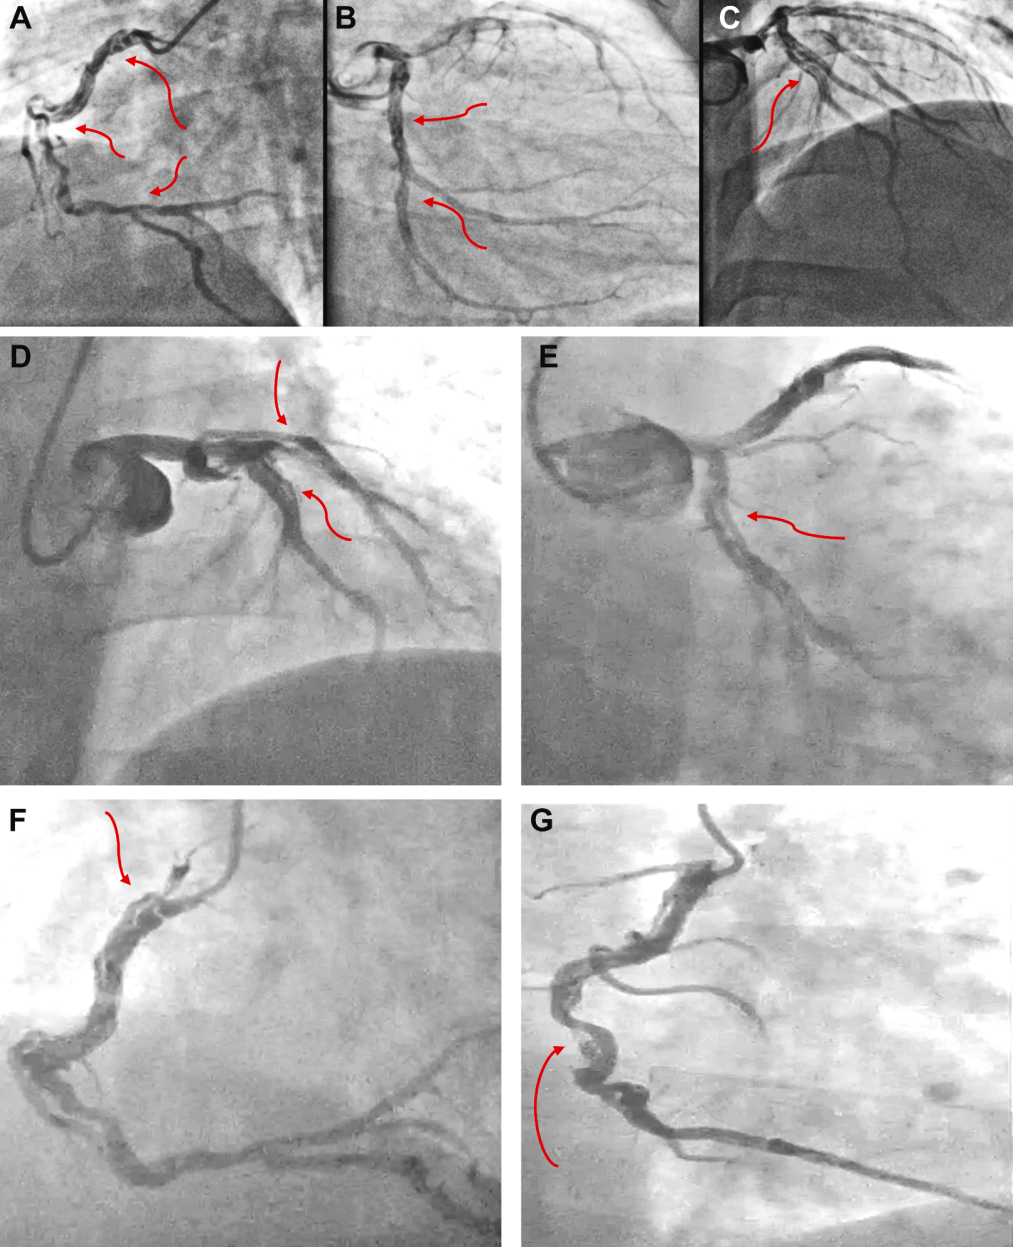

一位38岁男性健美运动员,因劳力性呼吸困难加重就诊。他曾于2018年发生下壁ST段抬高型心肌梗死(STEMI),当时归因于疑似累及右冠状动脉(RCA)和左回旋支(LCX)的SCAD。(图1A至1C)

图1 病例1:血管造影

2018年在另一家中心,(A)右冠状动脉(RCA)疑似自发性冠状动脉夹层(SCAD)。(B)左回旋支动脉(LCX)和(C)可能遗漏的左前降支动脉(LAD)SCAD。2024年在我们中心,被解读为(D)近段 LAD 的 SCAD 以及(E)粗大非优势 LCX 的广泛 SCAD(红色箭头)并累及主要钝缘支(OMM),(F 和 G)右冠状动脉(RCA)自开口至后降支(PDA)和后左室支(PLV)的广泛 SCAD(红色箭头)。

2024年,复查造影显示疑似SCAD累及近端左前降支(LAD)、近端LCX延伸至钝缘支,以及从RCA开口至左室后支和后降支(图1D至1G)。患者左心室射血分数(LVEF)下降至35%-40%。